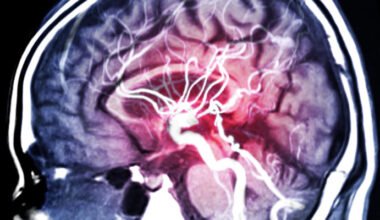

- Fizinė sveikata: Tai sveikas kūnas, gerai veikianti širdies ir kraujagyslių sistema, stiprūs raumenys ir kaulai, taip pat normali virškinimo sistema. Fizinė sveikata pasiekiama per subalansuotą mitybą, reguliarią fizinę veiklą ir tinkamą poilsį.